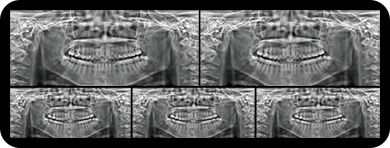

局部超清显示、 移动视野摄片

真人正侧位投影,实现CT成像区域无极可调

可根据临床需求任意调整成像区域大小实现局部超清三维显示

临床样片